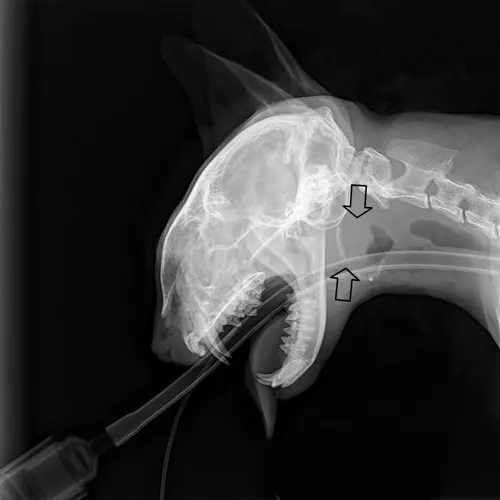

The polyp was incompletely removed, and the remaining portion cannot be removed with forceps via manual traction (Figure 4).

FIGURE 4 This nasopharyngeal polyp has a long thin stalk, which usually indicates that the root of the polyp has been retrieved.